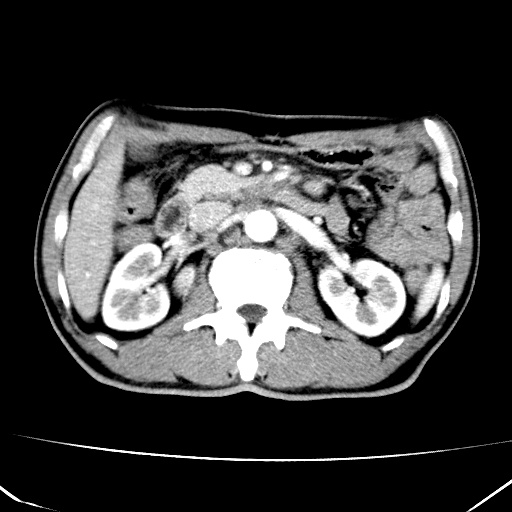

标题: CT17975:请求会诊。男、57岁。上腹部胀痛2天。临床诊断:糜 [打印本页]

标题: CT17975:请求会诊。男、57岁。上腹部胀痛2天。临床诊断:糜

肝脏多发类圆形低密度影,考虑肝脏转移瘤,肝胃韧带一淋巴结肿大,原发?胃癌?

考虑胃癌并肝脏及腹膜后淋巴结转移;不排除淋巴瘤。

肝内转移瘤,腹腔及腹膜后淋巴结转移。